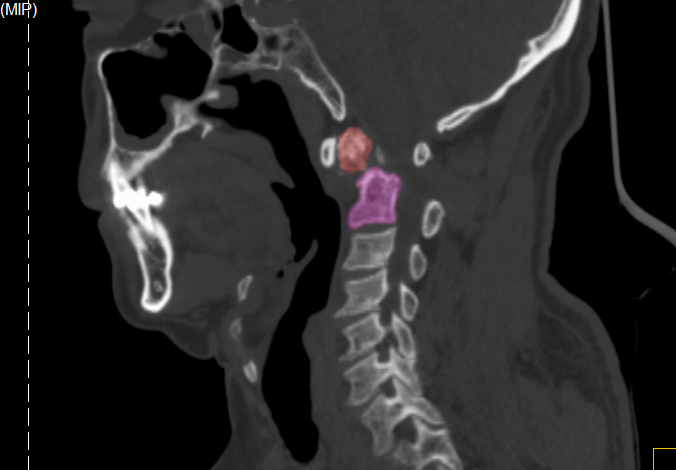

30年前,王先生頸部意外受傷,當時進行了保守治療,頸部疼痛一直伴隨他30余年。數年前王先生出現過無明顯誘因的雙上肢麻木、步態不穩等癥狀,但未予重視。

今年8月下旬,王先生因雙上肢酸痛、麻木難忍一月余才來就診。X線檢查顯示,王先生樞椎陳舊性骨折不愈合。脊柱創傷外科醫療團隊詳細評估認為,患者寰椎樞椎極度不穩定,隨時可能截癱進而危及生命,需盡快手術治療。此時,王先生毅然選擇手術,解決“折磨”了自己30余年“心頭大患”。

王先生術前CT